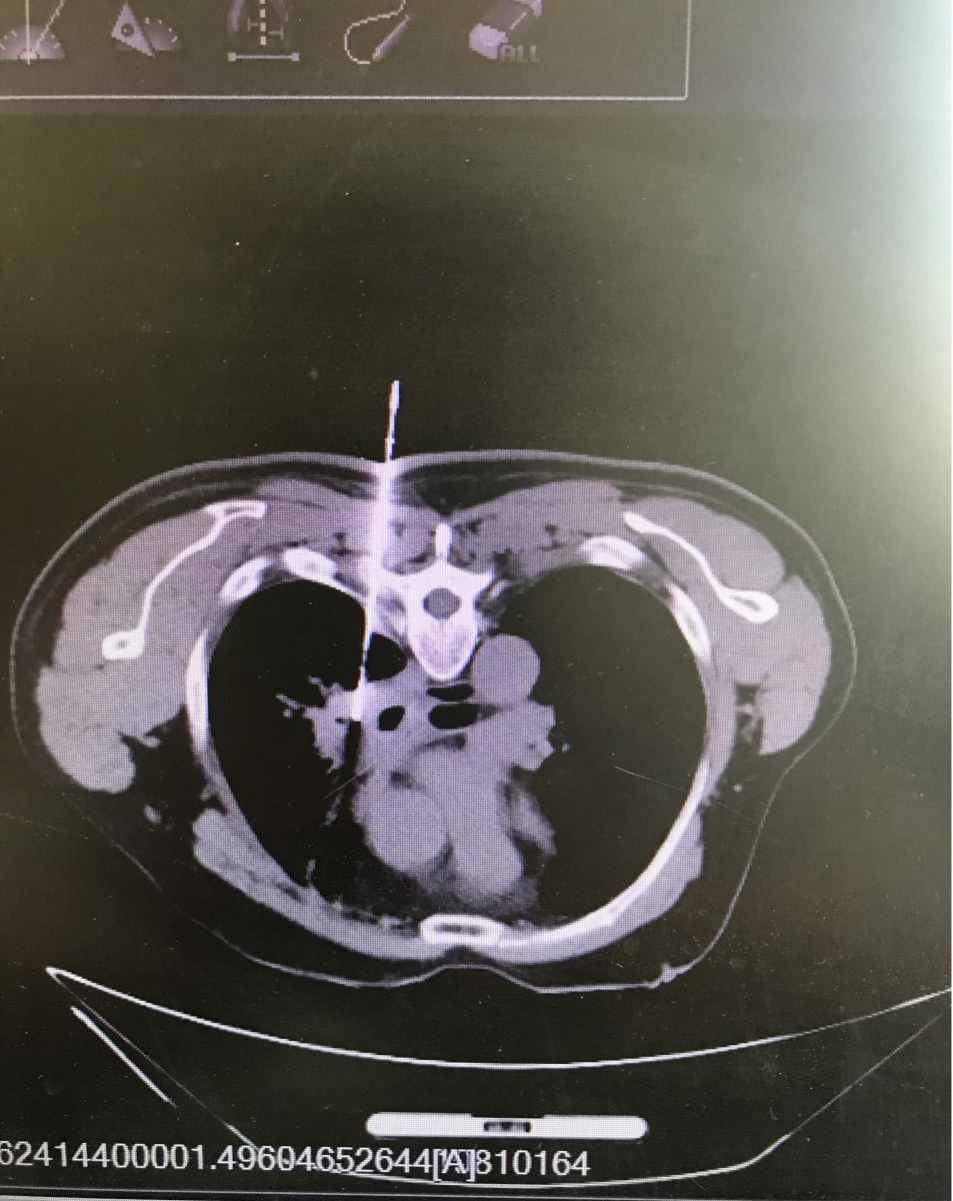

患者赵某,因咯痰中带血伴头晕1个月,来齐医附属一院肿瘤内科就诊,门诊检查C T及核磁共振发现自己得了肺癌,并且已经脑转移,顿时天像塌了一样,认为自己没有希望了。但是经过与医生的充分沟通后,他抱着试一试心态来治疗,肿瘤内科副主任付荣为他行肺肿块穿刺活检,明确了患者为肺腺癌,后给予了精准的个性化治疗2个周期后,患者所有的不适症状均得到的改善,复查一下CT和核磁共振效果显著。

我们可以看到,该患者满肺的转移病灶几乎清除殆尽,脑转移病灶缩小明显,大部分已经消失。